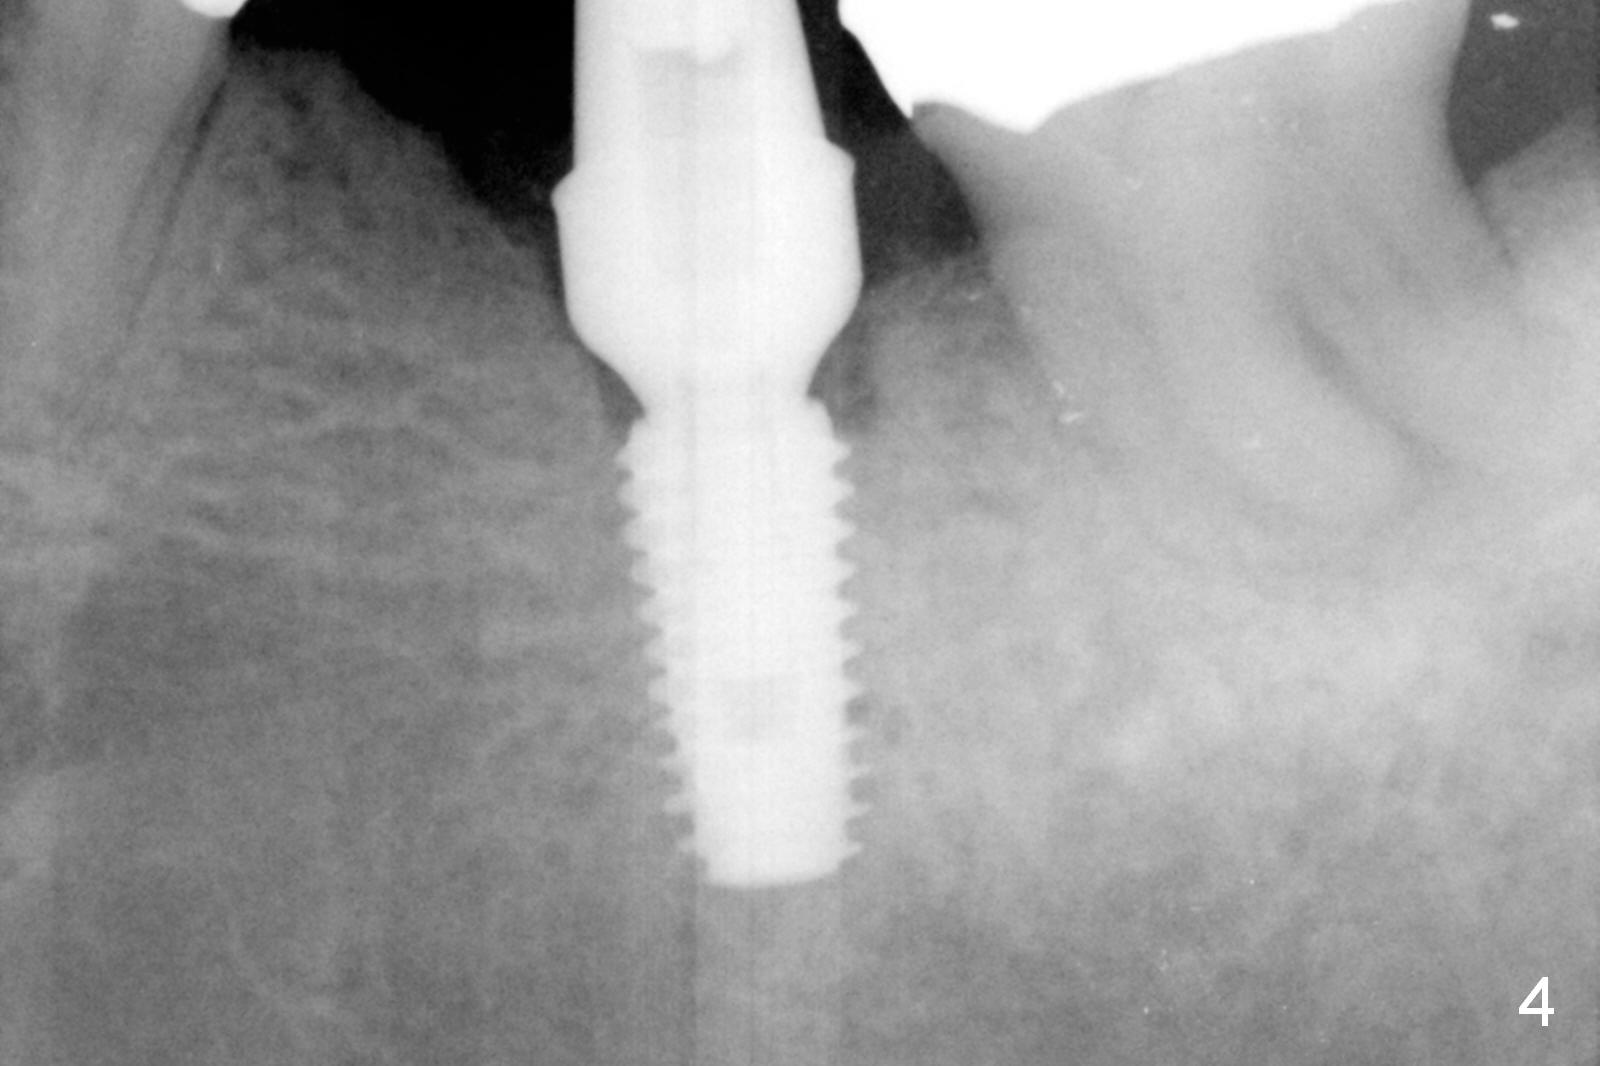

The narrow ridge top is trimmed until the buccolingual width is 7-8 mm; osteotomy starts in the flattened ridge (Fig.1, 2). A 5x10 mm implant is being placed (Fig.3). A cemented abutment (6.5x5.5(5) mm) is placed after adjusting the mesial and distal walls of the trimmed ridge (Fig.4). The patient returns for restoration 6 months postop. The coronal opening of the osteotomy becomes flared (Fig.5). The position and trajectory of the osteotomy should have been changed as early as possible (Fig.6, more or less parallel to the premolar) to avoid necessity of changing the cemented abutment (Fig.7 (* keratinized gingiva)) to an angled one (5.5 x15 degree A (4) mm).